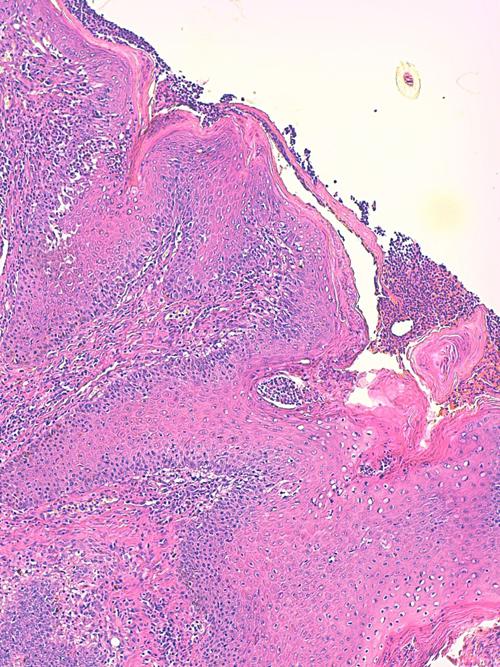

Photo 3 (Hémalun-Eosine X100) peau velue : Les infundibula folliculaires sont le siège d’une acanthose irrégulière et d’une hyperkératose (avec alternance d’ortho et de parakératose). Leur abouchement est souvent obstrué d’un matériel pustuleux. Leur gaine épithéliale externe présente des lignes de fissuration et de lyse des attaches desmosomiales des cellules épithéliales, dans lesquelles s’immiscent des granulocytes.

Légendes de la Photo 3 :

- Double flèche bleue pointillée : grand axe des infundibula folliculaires

- Ovales jaunes : pustules obstruant l’ostium ou l’infundibulum

- Flèches jaunes : fissuration linéaire dans la gaine épithélilae externe d’un follicule parallèle au grand axe de l’infundibulum

- Étoiles vertes évidées : hyperkératose orthokératosique

- Étoiles rouges pleines : hyperkératose parakératosique

- Étoiles turquoises pleines : infiltrat inflammatoire dermique périvasculaire à diffus